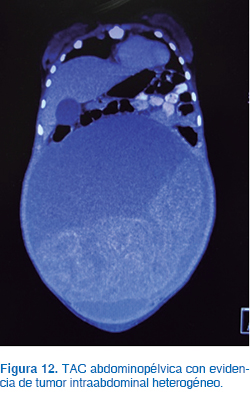

La TAC abdominopélvica evidenció un tumor intraabdominal heterogéneo (sólido y quístico) con densidades de 12 y 54 UH, sin calcificaciones, de 29 x 24 x 12 cm y peso de 4.61 kg (Figura 12). Los estudios de laboratorio mostraron alfa fetoproteína de 1.8 μg/L, fracción β de la gonadotrofina coriónica de 1.2 mUI/mL; LH, 6 mUI/mL; FSH, 7 mUI/mL; prolactina, 1,230 ng/mL (valor normal de referencia 0-20 ng/mL); estradiol, 2.1 pg/mL, y 17-OH PROG, 0.5 ng/dL.